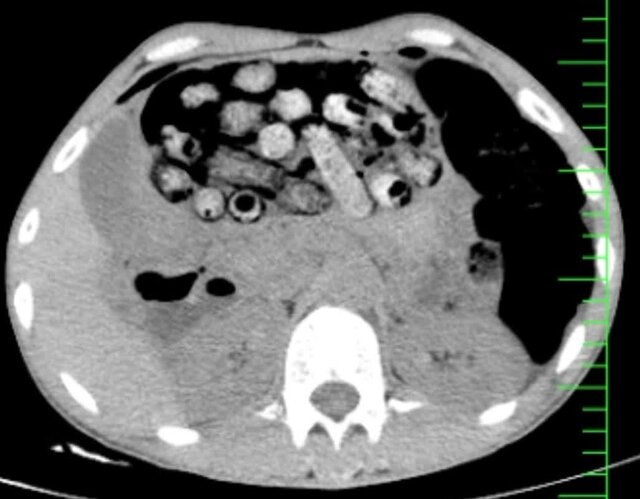

براساس اطلاعات اولیه مأمور همراه، بیمار پیش از مراجعه، اقدام به بلع تعدادی بسته محتوی مواد مخدر کرده بود. در پی انجام تصویربرداری فوری، تعداد زیادی بسته مشکوک در معده و روده کوچک و بزرگ وی مشاهده شد.

با توجه به خطر بالای پارگی احتمالی بستهها و بروز عوارض تهدیدکننده حیات، بیمار بلافاصله به اتاق عمل منتقل شد و جراحی سنگین وی از ساعت سه بامداد آغاز شد.

در این جراحی که به سرپرستی دکتر سامان شیخی، عضو هیأت علمی گروه جراحی عمومی دانشگاه علوم پزشکی البرز و با همکاری تیمهای اورژانس، تصویربرداری، بیهوشی و جراحی انجام و ۹۰ بسته از معده و روده بیمار خارج شد.